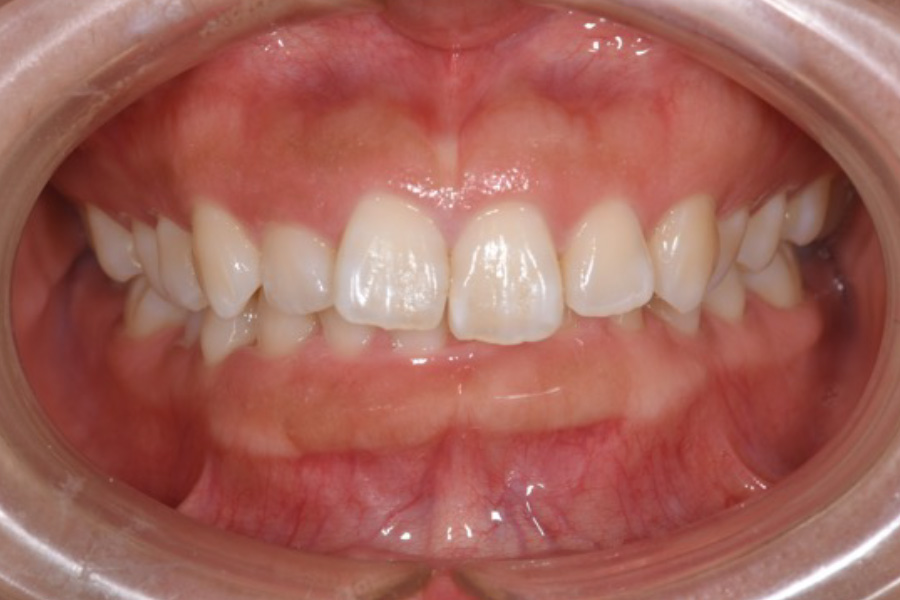

前歯がガタついている

【マウスピース矯正】

- 担当医

- -

- 主訴

- かみ合わせが悪い。前歯がガタついている。

- 期間

- 1年

- 費用

- マウスピース矯正

665,500円(税込)(2025年現在)

- 治療内容

- 目立ちにくいマウスピース矯正(非抜歯矯正)

歯と歯の間に隙間をつくることにより、歯列弓を広げながら治療を行いました。

- 治療に伴うリスク

- ・後戻りする可能性があるのでリテーナーを最低でも矯正期間以上はつけること

・稀にほっぺた、唇、舌などに口内炎や傷ができることがあります